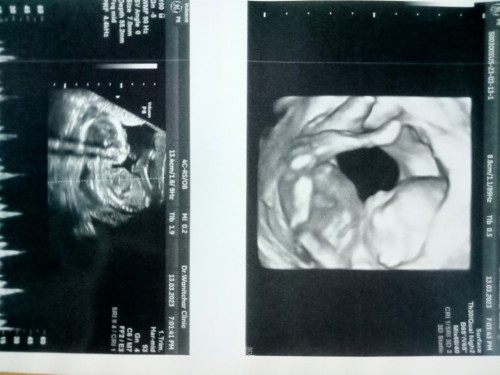

ภาพตอน14วีคค่ะ ตอนนี้16แล้ว #มิถุนา